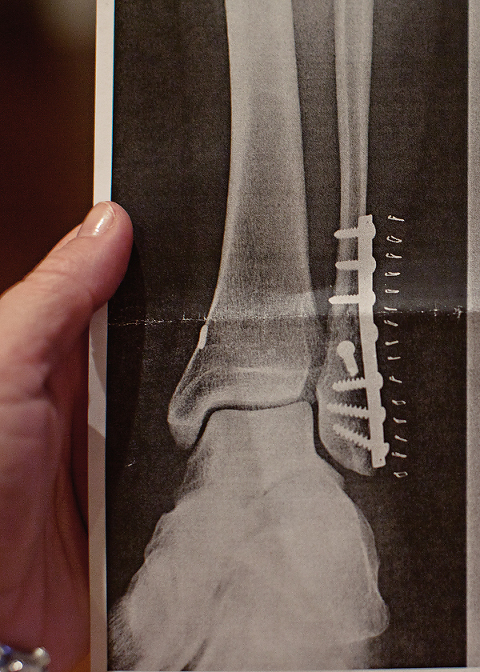

During the surgery, his doctor fixed it all up with some hardware, stapled him up, and put a cast on. I won’t bore you with the details of how awful he was to those poor nurses in recovery, or how when he found out I was only allowed 10 minutes back to see him every 4 hours he started pulling off wires and cussing. I certainly won’t explain how the nurses had to call his doctor at his request less than 2 hours after surgery and ask if he could be released to go home when he really should have stayed the night. I definitely won’t disclose that those same poor nurses couldn’t kick his ass out fast enough, and had him safely buckled in my front seat 10 minutes later heading back to Ocean Springs. Good times, good times… Scott’s cast stayed on for 10 days, then we went back to have the staples removed.

When he showed us the x-ray, I couldn’t help but ask about that one errant screw. It looked like the doc just dropped one in there by accident and forgot all about it.

He assured me that the errant screw had a purpose, and he didn’t seem like it bothered him that I was questioning his mad surgery skills. Come on, you know that screw looked wrong!!!.jpg)